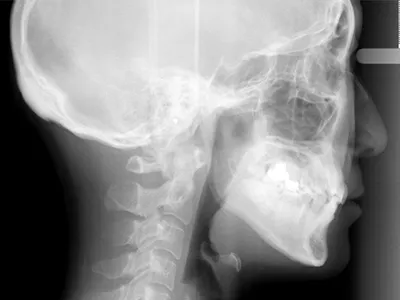

肉眼では見えない初期むし歯を発見します。デジタルデータの為、お口の中の情報をモニターですぐに確認できます。また、従来のレントゲンとくらべて被ばく量が1/10ほどに抑えられるため、身体にやさしいのが特徴です。当院ではセファロという矯正治療専用のレントゲンも完備しており、頭部も含めて精度の高い診査診断が可能となります。

セファロで撮影した高精度の画像から歯列弓や顎、骨格や歯などの現状や位置の移動を細かく分析し、スピーディかつ的確に様々な情報を把握するのに役立ちます。